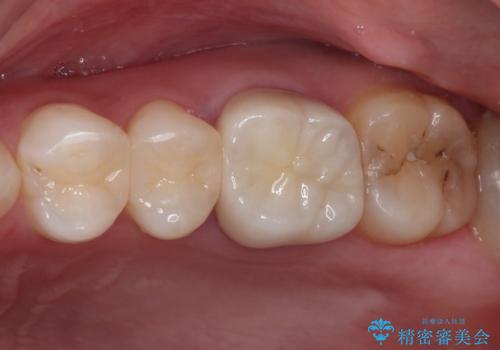

口腔内から、土台も含め銀歯がなくなったことでメタルフリーとなりました。